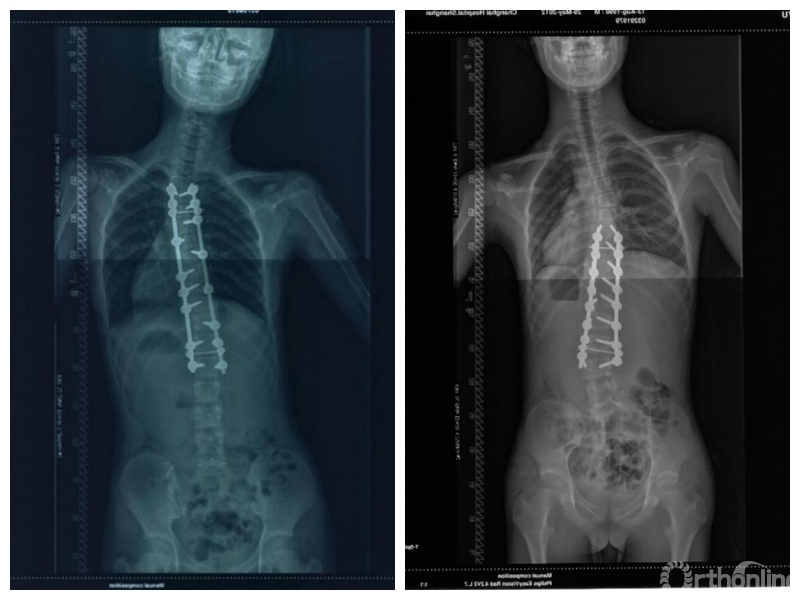

Wang等人[1]于2011年在Spine杂志上发表的文章中将远端附加现象定义为结构性主弯融合术后随访1年及以上时,主弯范围延长,最下固定椎(lowest instrumented vertebra,LIV)下方有更多椎体进入主弯,LIV以下第一个椎体偏离骶骨中垂线(center sacral vertical line,CSVL)5mm以上或LIV以下第一个椎间隙成角增加5°以上的现象。目前这一定义得到学界广泛的认可。远端附加现象多出现于行选择性胸弯融合的患者,主要是Lenke 1A型及Lenke 2A型AIS患者。其诊断标准为末次随访时,对比术后站立位脊柱全长正位片出现:

(1)主弯下端椎(lower end vertebra,LEV)向远端移动,主弯椎体数增加,LIV偏离CSVL 10mm以上;

(2)或是LIV以下第一个椎体偏离CSVL 5mm以上;

(3)或是LIV以下第1个椎间隙成角增加5°以上[1,2]。

而Upasani等人[6]对89例AIS患者进行回顾性分析发现,术后2年共13例患者出现远端附加现象,其中年龄小及Risser征较低为独立危险因素,因此认为骨骼成熟度越低的患者术后更易发生远端附加现象,进而提出远端附加现象可认为是随年龄增长而在远端新发的侧凸。同时,Murphy等人[7]及国内李明教授团队[8]的研究也证实,Risser征低(0级或1级)的AIS病人术后更易出现远端附加现象。进而部分学者认为骨骼发育不成熟的AIS患者进行融合术后,随着骨骼的发育,远端逐渐形成新的侧凸,最终成为远端附加现象。

最后实质触及椎是LIV的最佳选择[8]

国内邱勇教授团队[12]回顾性分析104例Lenke 1A型AIS患者,其中23例(22.1%)发生远端附加现象,分析认为LIV的选择应位于最后实质触及椎(从骶骨往头端最后一个被CSVL平分的椎体)以降低远端附加现象发生率。此外,李明教授团队[13-15]的系列研究也认为选择最后实质触及椎作为LIV,术后发生远端附加现象的风险最低,同时应该考虑LIV距离CSVL不应超过1cm。因此,学界认为对于AIS患者行选择性胸弯融合手术的LIV应选择最后实质触及椎最为合适。